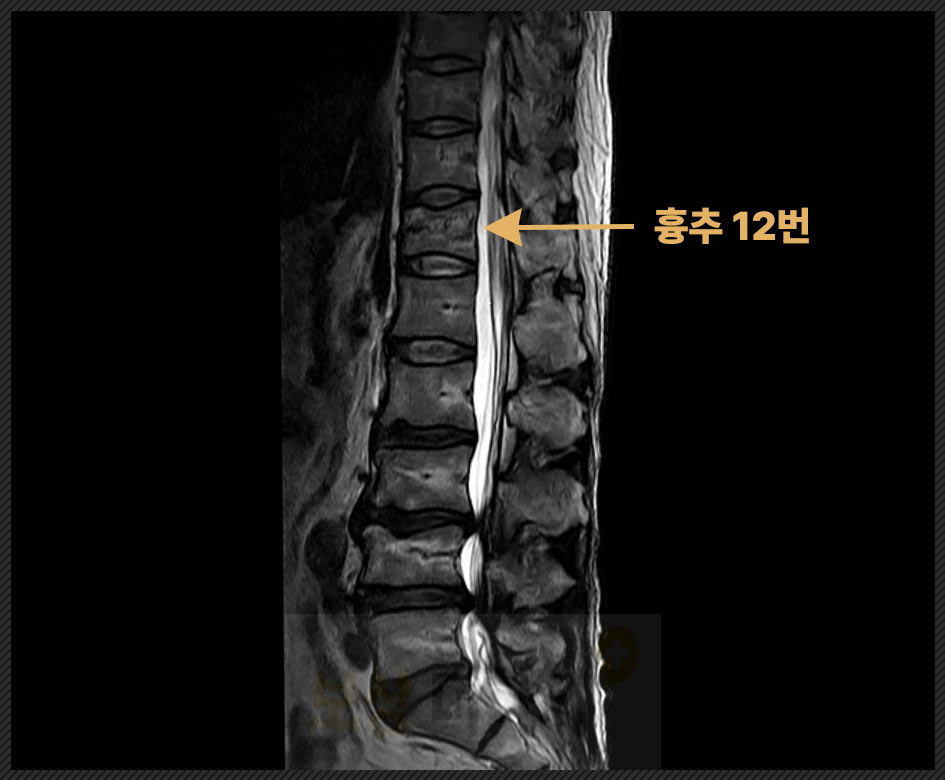

▶ 사고 경위 길에서 넘어짐 ▶ 진단명 흉추 12번 압박골절 ▶ 치료 척추체 성형술

생리적 만곡을 고려한 후만 변형 정도, 압박률 등을 유리한 시기에 평가받았고 약관상 척추에 뚜렷한 기형을 남긴 때, 지급률 30%에 해당한다는 점을 근거로 보험금 산정을 한 후에 최종 800만 원 이상을 지급받으셨습니다. * 이 과정에서 발생할 수 있는 분쟁을 사전에 대비하였으며, 감액 주장에도 논리적 근거를 바탕으로 적극 반박했습니다. → 결과, 합리적인 보상으로 마무리할 수 있었습니다.